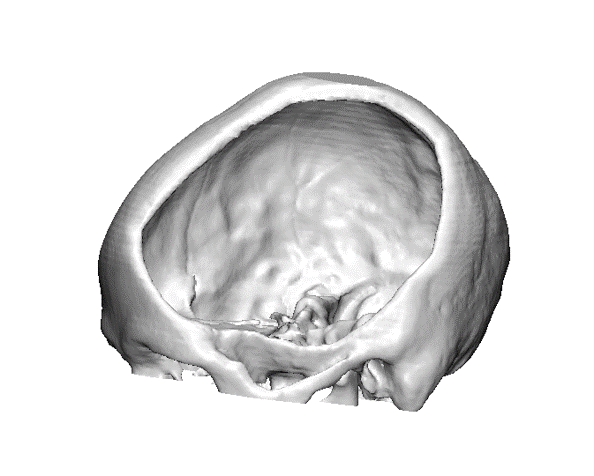

Sin Puente

Defectos con bordes irregulares.